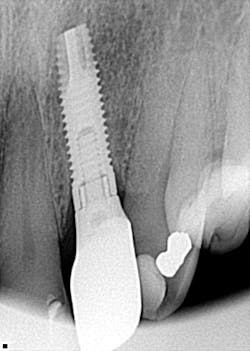

1. Coronal—abutment interface, flange, and collar (figure 4)

Figure 4

2. Mid-body—implant taper, implant threads, thread type, mid-body grooves (figure 5)

3. Apical—apex shape, open apex, round hole, apical chamber, apical grooves (figure 6)

Figure 6

- According to Dr. Howell, if there is one thing that can help you the most to identify an implant, it’s to look at the apex.